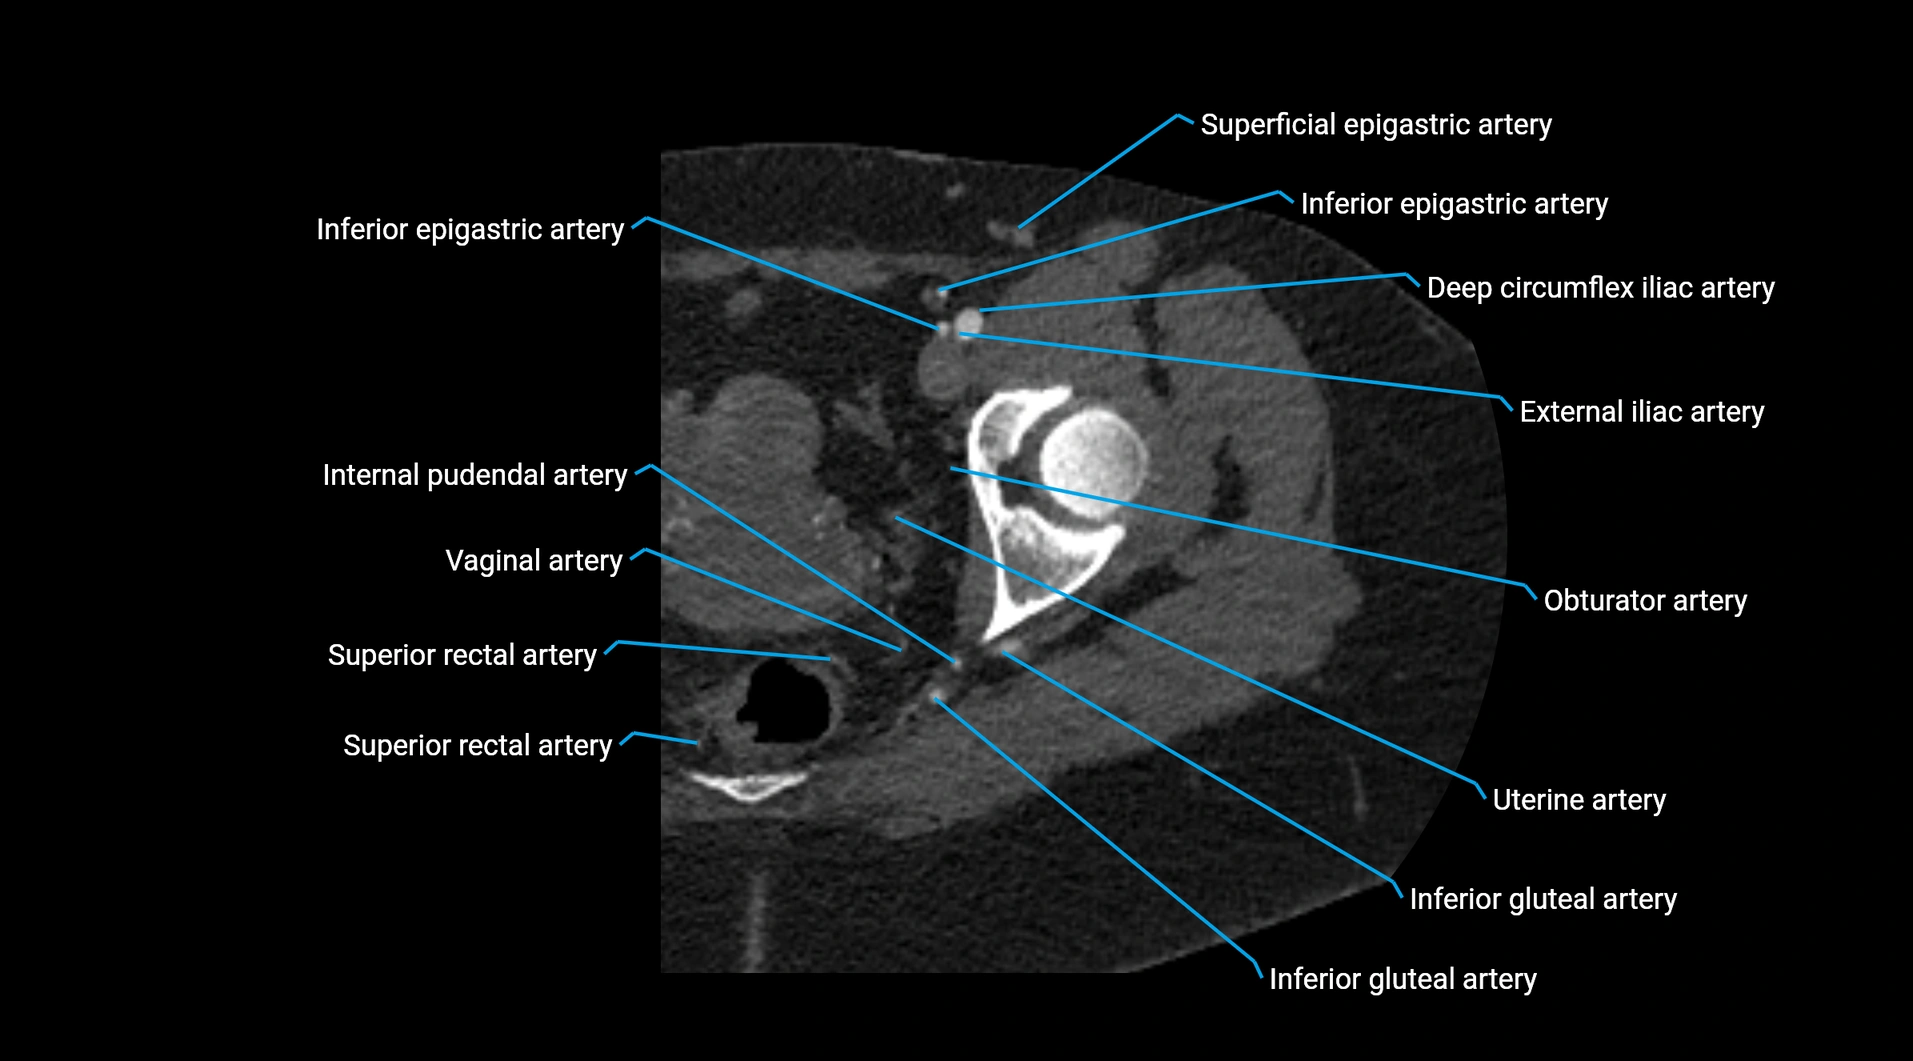

Contrast-enhanced CT (CTA):

• Gold standard for abdominal aortic imaging

• Provides excellent detail of lumen, wall, aneurysm, thrombus, and branch vessels

• Multiplanar and 3D reconstructions help in aneurysm measurement, stent graft planning, and dissection evaluation

• Detects acute rupture, traumatic injury, or occlusion with high sensitivity